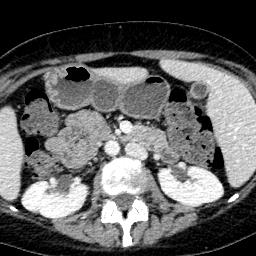

Due to the constraints of the imaging device and high cost in operation time, computer tomography (CT) scans are usually acquired with low intra-slice resolution. Improving the intra-slice resolution is beneficial to the disease diagnosis for both human experts and computer-aided systems. To this end, this paper builds a novel medical slice synthesis to increase the between-slice resolution. Considering that the ground-truth intermediate medical slices are always absent in clinical practice, we introduce the incremental cross-view mutual distillation strategy to accomplish this task in the self-supervised learning manner. Specifically, we model this problem from three different views: slice-wise interpolation from axial view and pixel-wise interpolation from coronal and sagittal views. Under this circumstance, the models learned from different views can distill valuable knowledge to guide the learning processes of each other. We can repeat this process to make the models synthesize intermediate slice data with increasing inter-slice resolution. To demonstrate the effectiveness of the proposed approach, we conduct comprehensive experiments on a large-scale CT dataset. Quantitative and qualitative comparison results show that our method outperforms state-of-the-art algorithms by clear margins.